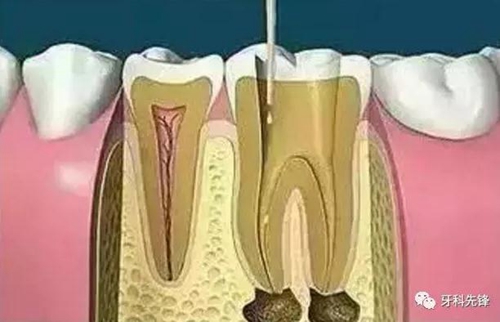

3、確定根管工作長度

應(yīng)用平行投照X線方法、根管長度測量儀確定根管度,最好插針拍X片。